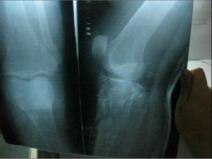

La police l’a finalement envoyé à l’hôpital de Daqing pour faire des radios, qui ont révélé que la jambe de M. Jiao portait de multiples fractures. Après, les policiers ont reconduit M. Jiao au commissariat mais ne voulait pas le laisser sortir de la voiture car des responsables municipaux tenaient une réunion à l’intérieur. Un chef de la police est sorti du commissariat et a dit à M. Jiao : « Nous allons vous relâcher. Avez-vous de la famille à Daqing ? Ils peuvent vous ramener chez vous et soigner votre jambe. »

Comme il n’a pas été soigné rapidement, sa jambe fracturée et son pied ont sérieusement enflé, et ont presque doublé de volume. A ce jour, sa jambe n’est toujours pas complètement guérie.

Ci-dessous des photos de la jambe cassée de M. Jiao Long :